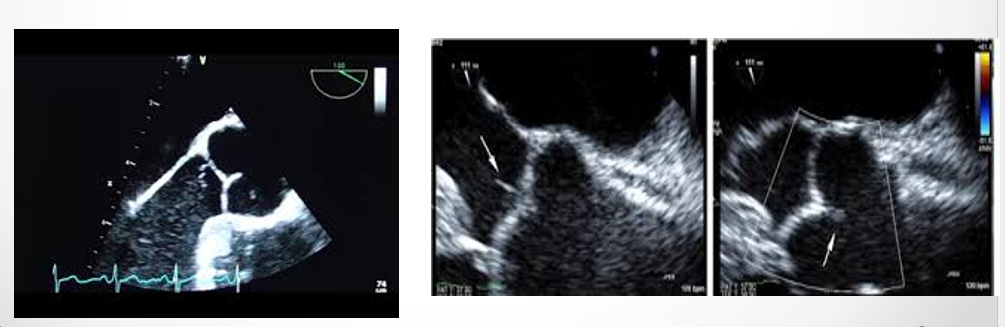

what is seen here?

tricuspid valve vegetation w/ severe regurg